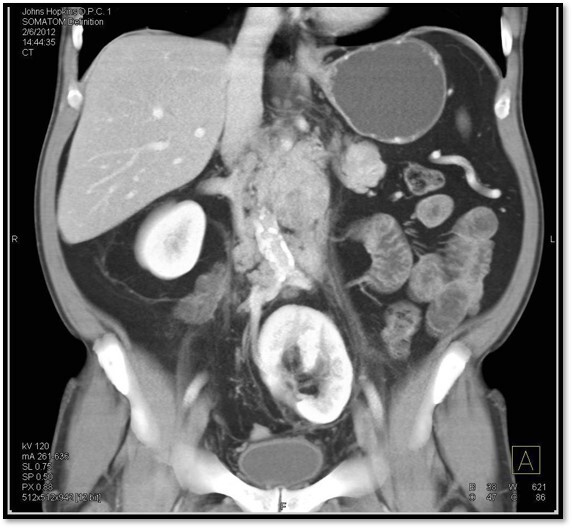

24

Q

What pathology is seen here?

A

Urinary Calculi